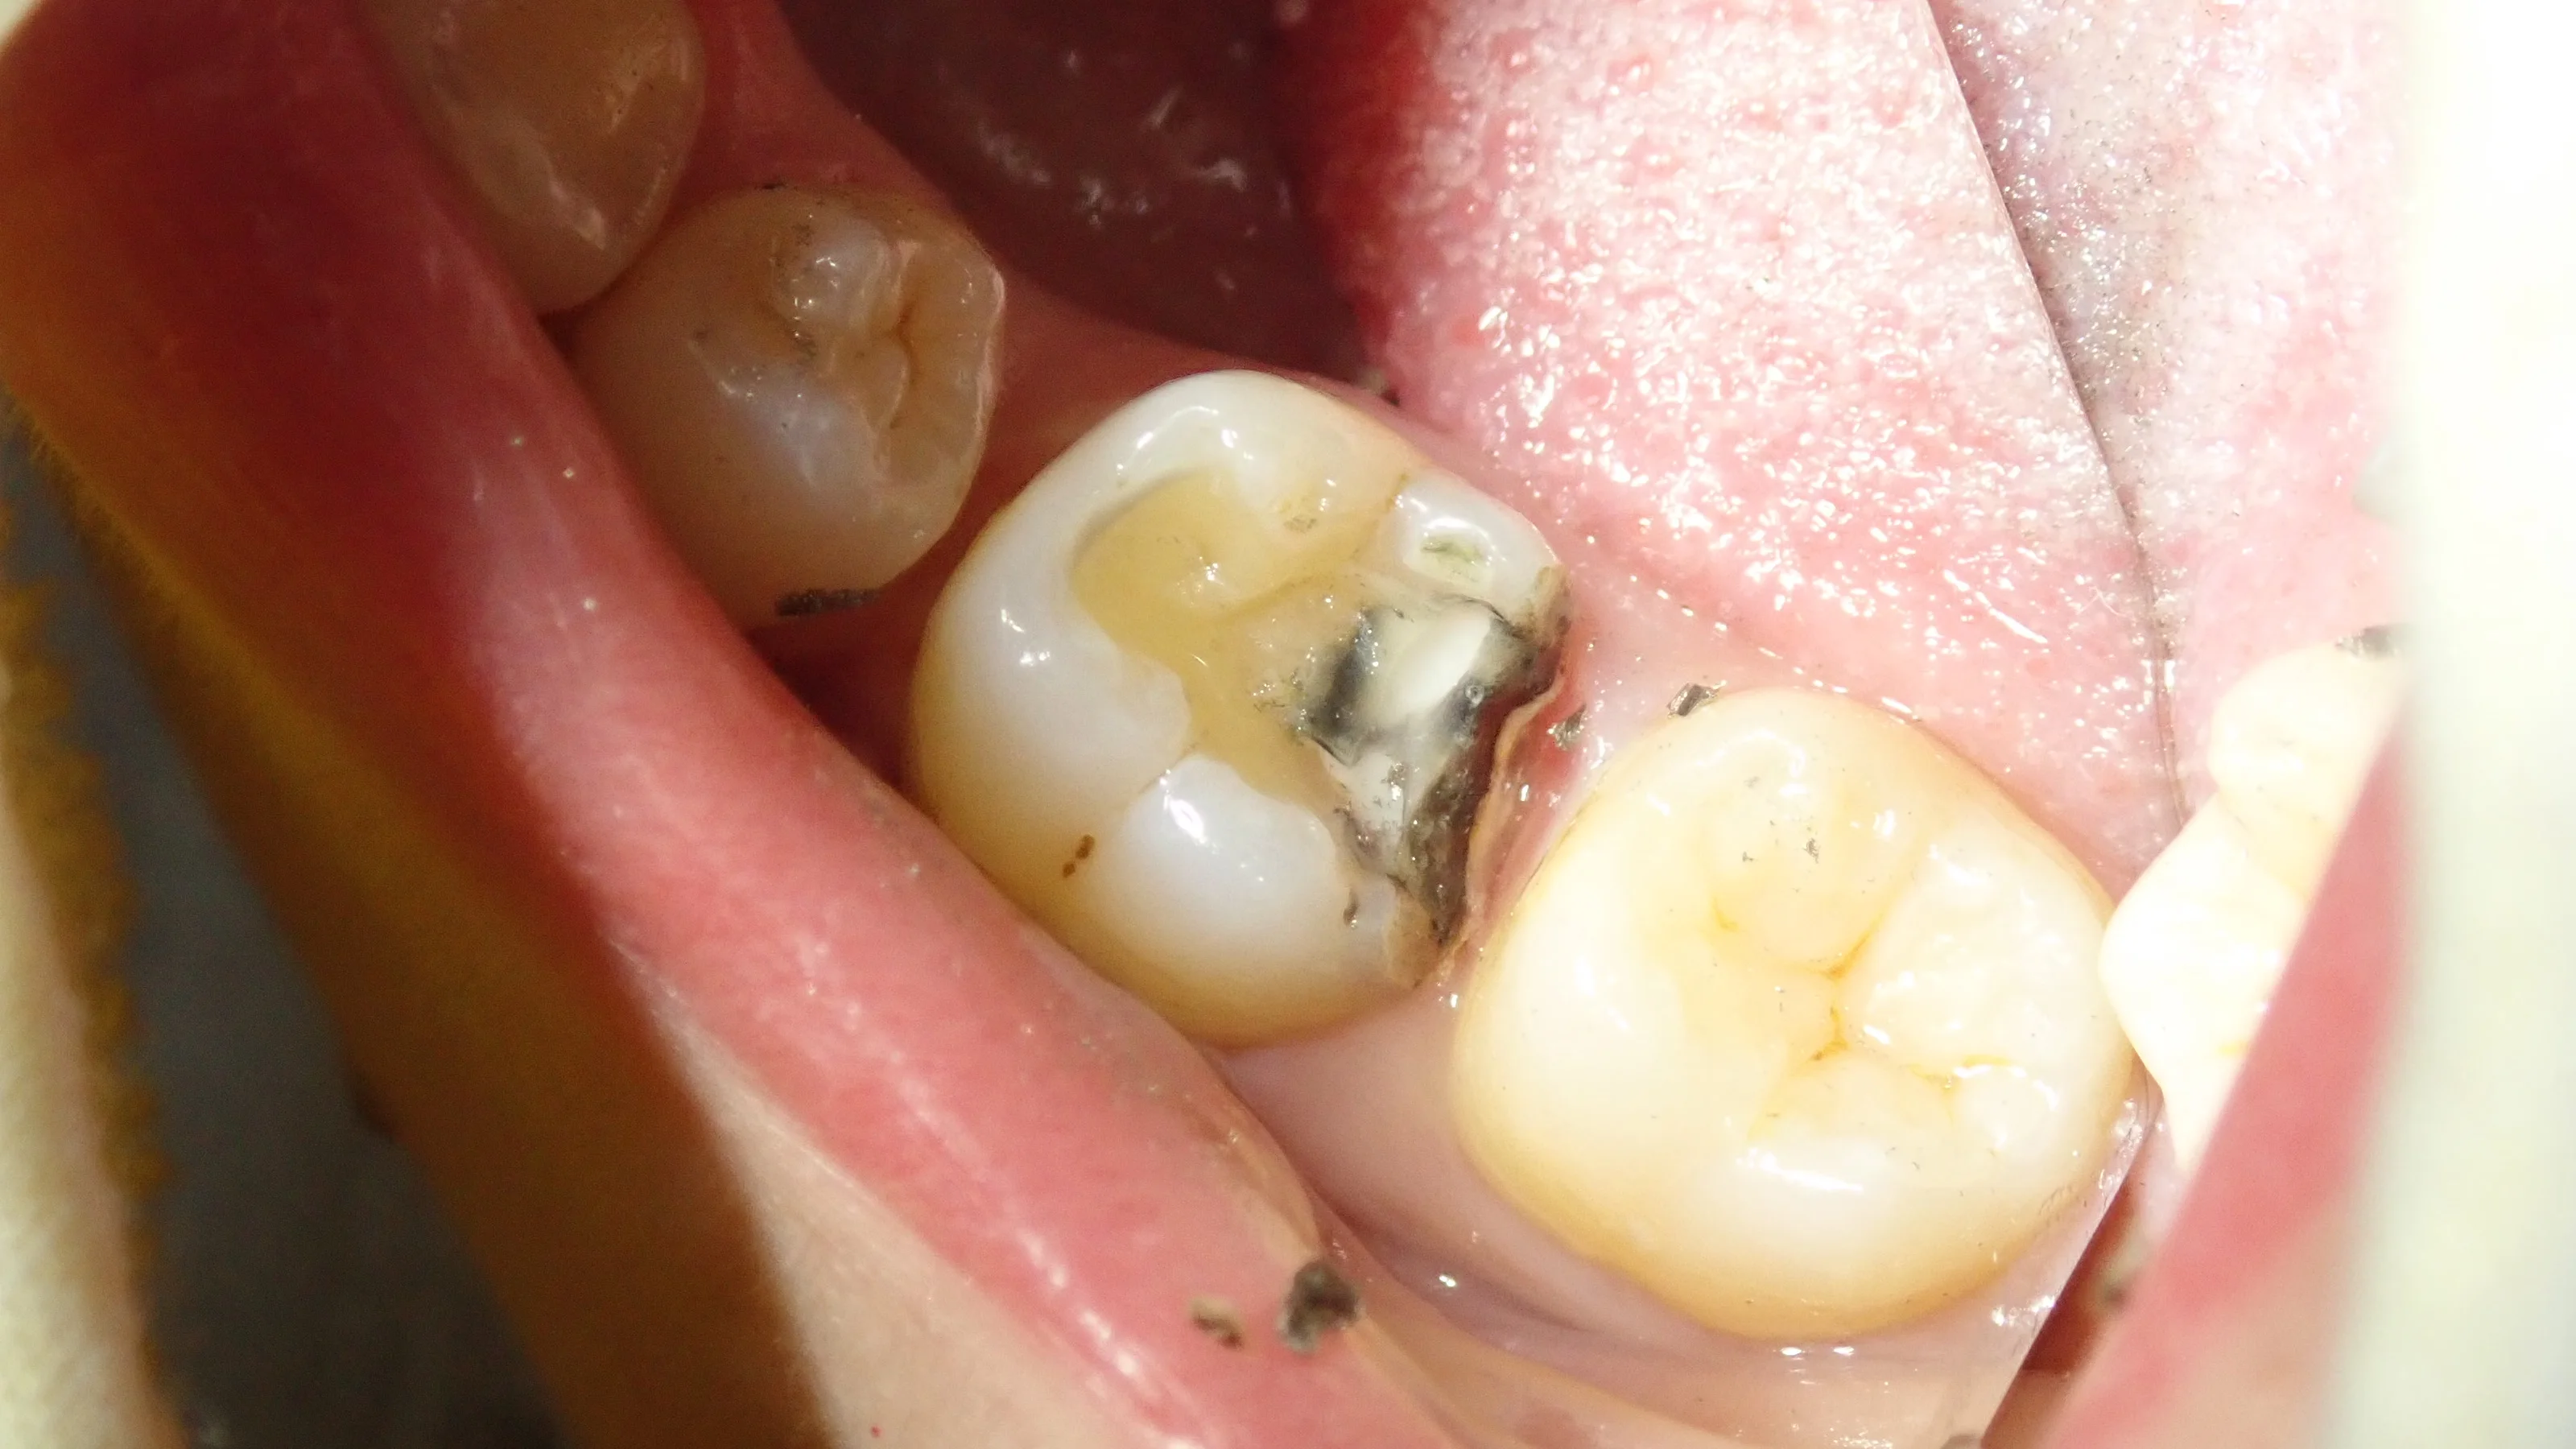

で、完全に虫歯を取り切ったらこうなりました。

後ろの歯との間が非常に深くなっています。

手前の歯との間についても、虫歯だったため、歯が少なくなってしまいました。

そして、詰め終わったのがこちら

スペースが非常に大きかったため、半ば無理矢理スペースを埋めました。

歯科医療従事者の方なので、ブラッシングなどはしっかりと行ってもらえるでしょう・・・!

良好な結果を得ることができました。

しっかりと歯磨き・フロスなどを頑張って、なるべく長持ちさせていただきたいですね!